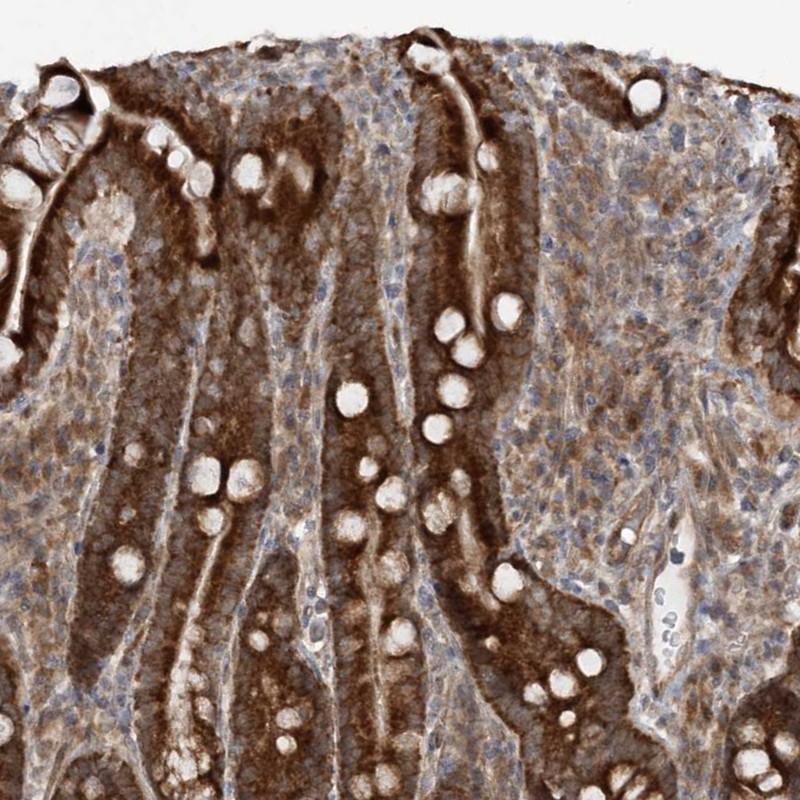

Immunohistochemical staining of human duodenum shows strong cytoplasmic positivity in glandular cells.